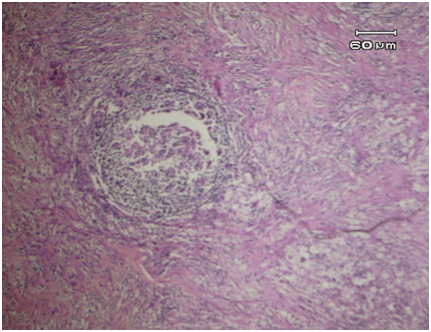

The characteristic of microscopic features in XGP including a mixture of neutrophils, lymphocytes plasma, histiocytes or macrophages and giant cells. The patognomonic signs are the foamy histiocytes or macrophages (xanthomatous) consist of fat droplets (lipid-laden foamy macrophage). Sometimes, cholesterol crystals and fibrous tissue may reveal. The macroscopic and microscopic appearances of XGP are very similar with renal cell carcinoma (RCC) where the foamy macrophages in XGP contain microvesicular sitoplasm similar with the RCC cells. The difference within both entities is the inflammation background in XGP and there are no pleomorpic cells and mitotic figures. In some difficult cases, Immunohistochemistry staining should be performed. The foamy macrophage in XGP shows negative with cytokeratin and vimentin stains whereas positive for lysozime stain.3 The treatment of XGP is surgery consist of nephrectomy and it have a good prognosis if the infection only affect one kidney.

A 30 years old female with previous clinical diagnose of ovarian cyst. During the surgery they revealed that the cyst is not at the ovary but at the kidney, thus the partial nephrectomy was performed. Macroscopic examination reveals a 15x14x10cm tissues consist of multiple small cysts with brown thick septae (Figure 1). Microscopic examination shows kidney tissues with granulomatous inflammation. The glomeruli hialinated, atrophy of tubules and some with thyroidisatio (Figure 2). It also shows abundant foamy macrophages and granulomatous (Figure 3).

Figure 3 Macrophages contain “foamy cytoplasm”. Pathognomonic sign of XGP.

XGP is a rare variant of pyelonephritis which is more common in women, usually affects unilateral kidney and associated with nephrolithiasis.3 There is one reported case of XGP in 40years old male with staghorn calculus but nephrolithiasis is not found in our case. Macroscopically, the affected kidneys enlarge, contain cysts formation, yellowish masses and dilated calices which can be found in our case. The destruction of affected all renal parenchyma in almost all cases which have been reported. The normal structures of kidney replaced by cystic structures as in hydronephrosis obstruction. The tipycal microscopic appearance of XGP consists of large macrophages with vacuolated sitoplasm, mononuclear inflammatory cells including plasma cells and lymphocyte. In this case we found a large number of foamy macrophage with vacuolated sitoplasm, arrange in granulomatous structures and several giant cells (Figure 4). We also found the features of classic chronic pyelonephritis which are interstitial inflammatory infiltration and tubules thyroidisation (Figure 2).2,3,7,8

Figure 4 Xanthomatous cells arrange in granulomatic form.